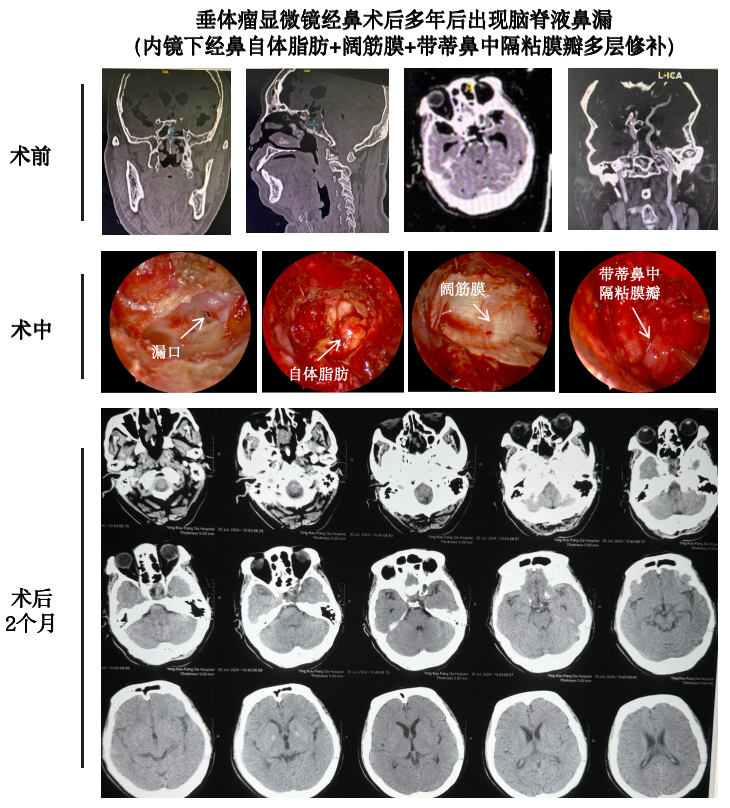

什么是腦脊液鼻漏?腦脊液鼻漏是指腦脊液(CSF)通過(guò)顱底缺損,從鼻腔或鼻竇流出的病理狀態(tài)。這種情況通常是由于顱底骨折、手術(shù)損傷、顱內(nèi)壓力升高或自發(fā)性原因?qū)е?。腦脊液鼻漏若不及時(shí)處理,可能導(dǎo)致顱內(nèi)感染(如腦膜炎),需要引起重視。腦脊液鼻漏的類型1.根據(jù)病因分類?創(chuàng)傷性鼻漏:?最常見(jiàn),常見(jiàn)于頭部外傷或顱底骨折后。?也可能發(fā)生在顱底手術(shù)(如垂體瘤手術(shù))后。?自發(fā)性鼻漏:?無(wú)明顯外傷或手術(shù)史,多與顱內(nèi)壓升高相關(guān)。?常見(jiàn)于肥胖或高顱壓患者。?醫(yī)源性鼻漏:?醫(yī)療干預(yù)或手術(shù)(如鼻竇手術(shù)、腦垂體手術(shù))引起的鼻漏。2.根據(jù)漏口位置分類?前顱底鼻漏:漏口位于篩板、額竇或蝶竇。?中顱底鼻漏:漏口多位于顳骨巖部,較為少見(jiàn)。3.根據(jù)持續(xù)時(shí)間分類?急性鼻漏:鼻漏發(fā)生時(shí)間較短,通常與近期創(chuàng)傷或手術(shù)相關(guān)。?慢性鼻漏:癥狀持續(xù)時(shí)間長(zhǎng),且可能伴有間歇性流液。腦脊液鼻漏的手術(shù)治療1.手術(shù)適應(yīng)癥?長(zhǎng)時(shí)間(超過(guò)7-10天)的持續(xù)鼻漏無(wú)法自行愈合。?合并腦膜炎或顱內(nèi)感染風(fēng)險(xiǎn)增加。?自發(fā)性或醫(yī)源性鼻漏難以通過(guò)保守治療控制。?鼻漏引起患者生活質(zhì)量下降或其他并發(fā)癥。2.手術(shù)方式(1)經(jīng)鼻內(nèi)鏡修補(bǔ)術(shù)?概述:最常用的微創(chuàng)手術(shù),通過(guò)鼻腔內(nèi)鏡定位漏口并修補(bǔ)缺損。?步驟:?確定漏口位置,去除周圍炎性或壞死組織。?使用自體組織(如脂肪、筋膜、粘膜瓣)或人工材料(如生物膠)進(jìn)行修補(bǔ)。?加用鼻竇填塞物以穩(wěn)定修補(bǔ)材料。?優(yōu)點(diǎn):創(chuàng)傷小、恢復(fù)快、住院時(shí)間短。?適應(yīng)癥:適用于前顱底漏口或篩板區(qū)域的鼻漏。(2)開(kāi)顱手術(shù)修補(bǔ)?概述:對(duì)于復(fù)雜漏口(如中顱底或顱底廣泛缺損),需要通過(guò)開(kāi)顱手術(shù)直接修補(bǔ)。?優(yōu)點(diǎn):更適合修補(bǔ)大面積或深部的顱底缺損。?缺點(diǎn):創(chuàng)傷較大,恢復(fù)時(shí)間較長(zhǎng)。3.手術(shù)目標(biāo)?完全修補(bǔ)漏口,恢復(fù)顱底完整性。?防止腦脊液進(jìn)一步外漏,降低腦膜炎等并發(fā)癥風(fēng)險(xiǎn)。術(shù)后管理與輔助治療1.基礎(chǔ)護(hù)理?臥床休息:術(shù)后數(shù)天需避免活動(dòng),以減少顱內(nèi)壓波動(dòng)。?頭部抬高:抬高頭部以減少顱內(nèi)壓,有助于傷口愈合。2.鼻腔護(hù)理?避免用力擤鼻涕,防止修補(bǔ)材料移位。?定期清理鼻腔,保持干凈,預(yù)防感染。3.藥物治療?抗生素:預(yù)防或治療術(shù)后可能發(fā)生的感染。?降顱內(nèi)壓藥物:如甘露醇,用于降低顱內(nèi)壓,促進(jìn)愈合。4.定期隨訪?術(shù)后1-3個(gè)月進(jìn)行影像學(xué)檢查(如CT或MRI),評(píng)估修補(bǔ)效果。?如復(fù)發(fā)鼻漏需盡早干預(yù)。5.生活管理?避免劇烈運(yùn)動(dòng)、咳嗽和便秘等增加顱內(nèi)壓的行為。?注意飲食清淡,避免攝入過(guò)多鹽分引起水鈉潴留。腦脊液鼻漏的預(yù)后?經(jīng)鼻內(nèi)鏡修補(bǔ)術(shù):成功率可達(dá)90%以上,復(fù)發(fā)率低。?開(kāi)顱手術(shù)修補(bǔ):適用于復(fù)雜病例,術(shù)后管理得當(dāng)也能獲得良好預(yù)后。?總體預(yù)后:及早診斷、合理治療,患者通??赏耆祻?fù),避免嚴(yán)重并發(fā)癥??破湛偨Y(jié)腦脊液鼻漏是一種可治愈的疾病,但若未及時(shí)治療,可能導(dǎo)致嚴(yán)重的顱內(nèi)感染。手術(shù)修補(bǔ)是關(guān)鍵治療手段,微創(chuàng)經(jīng)鼻內(nèi)鏡技術(shù)使患者受益良多。術(shù)后需要科學(xué)管理和定期隨訪,保障修補(bǔ)效果和長(zhǎng)期健康。及時(shí)就診,規(guī)范治療,保護(hù)顱腦健康!典型病例: